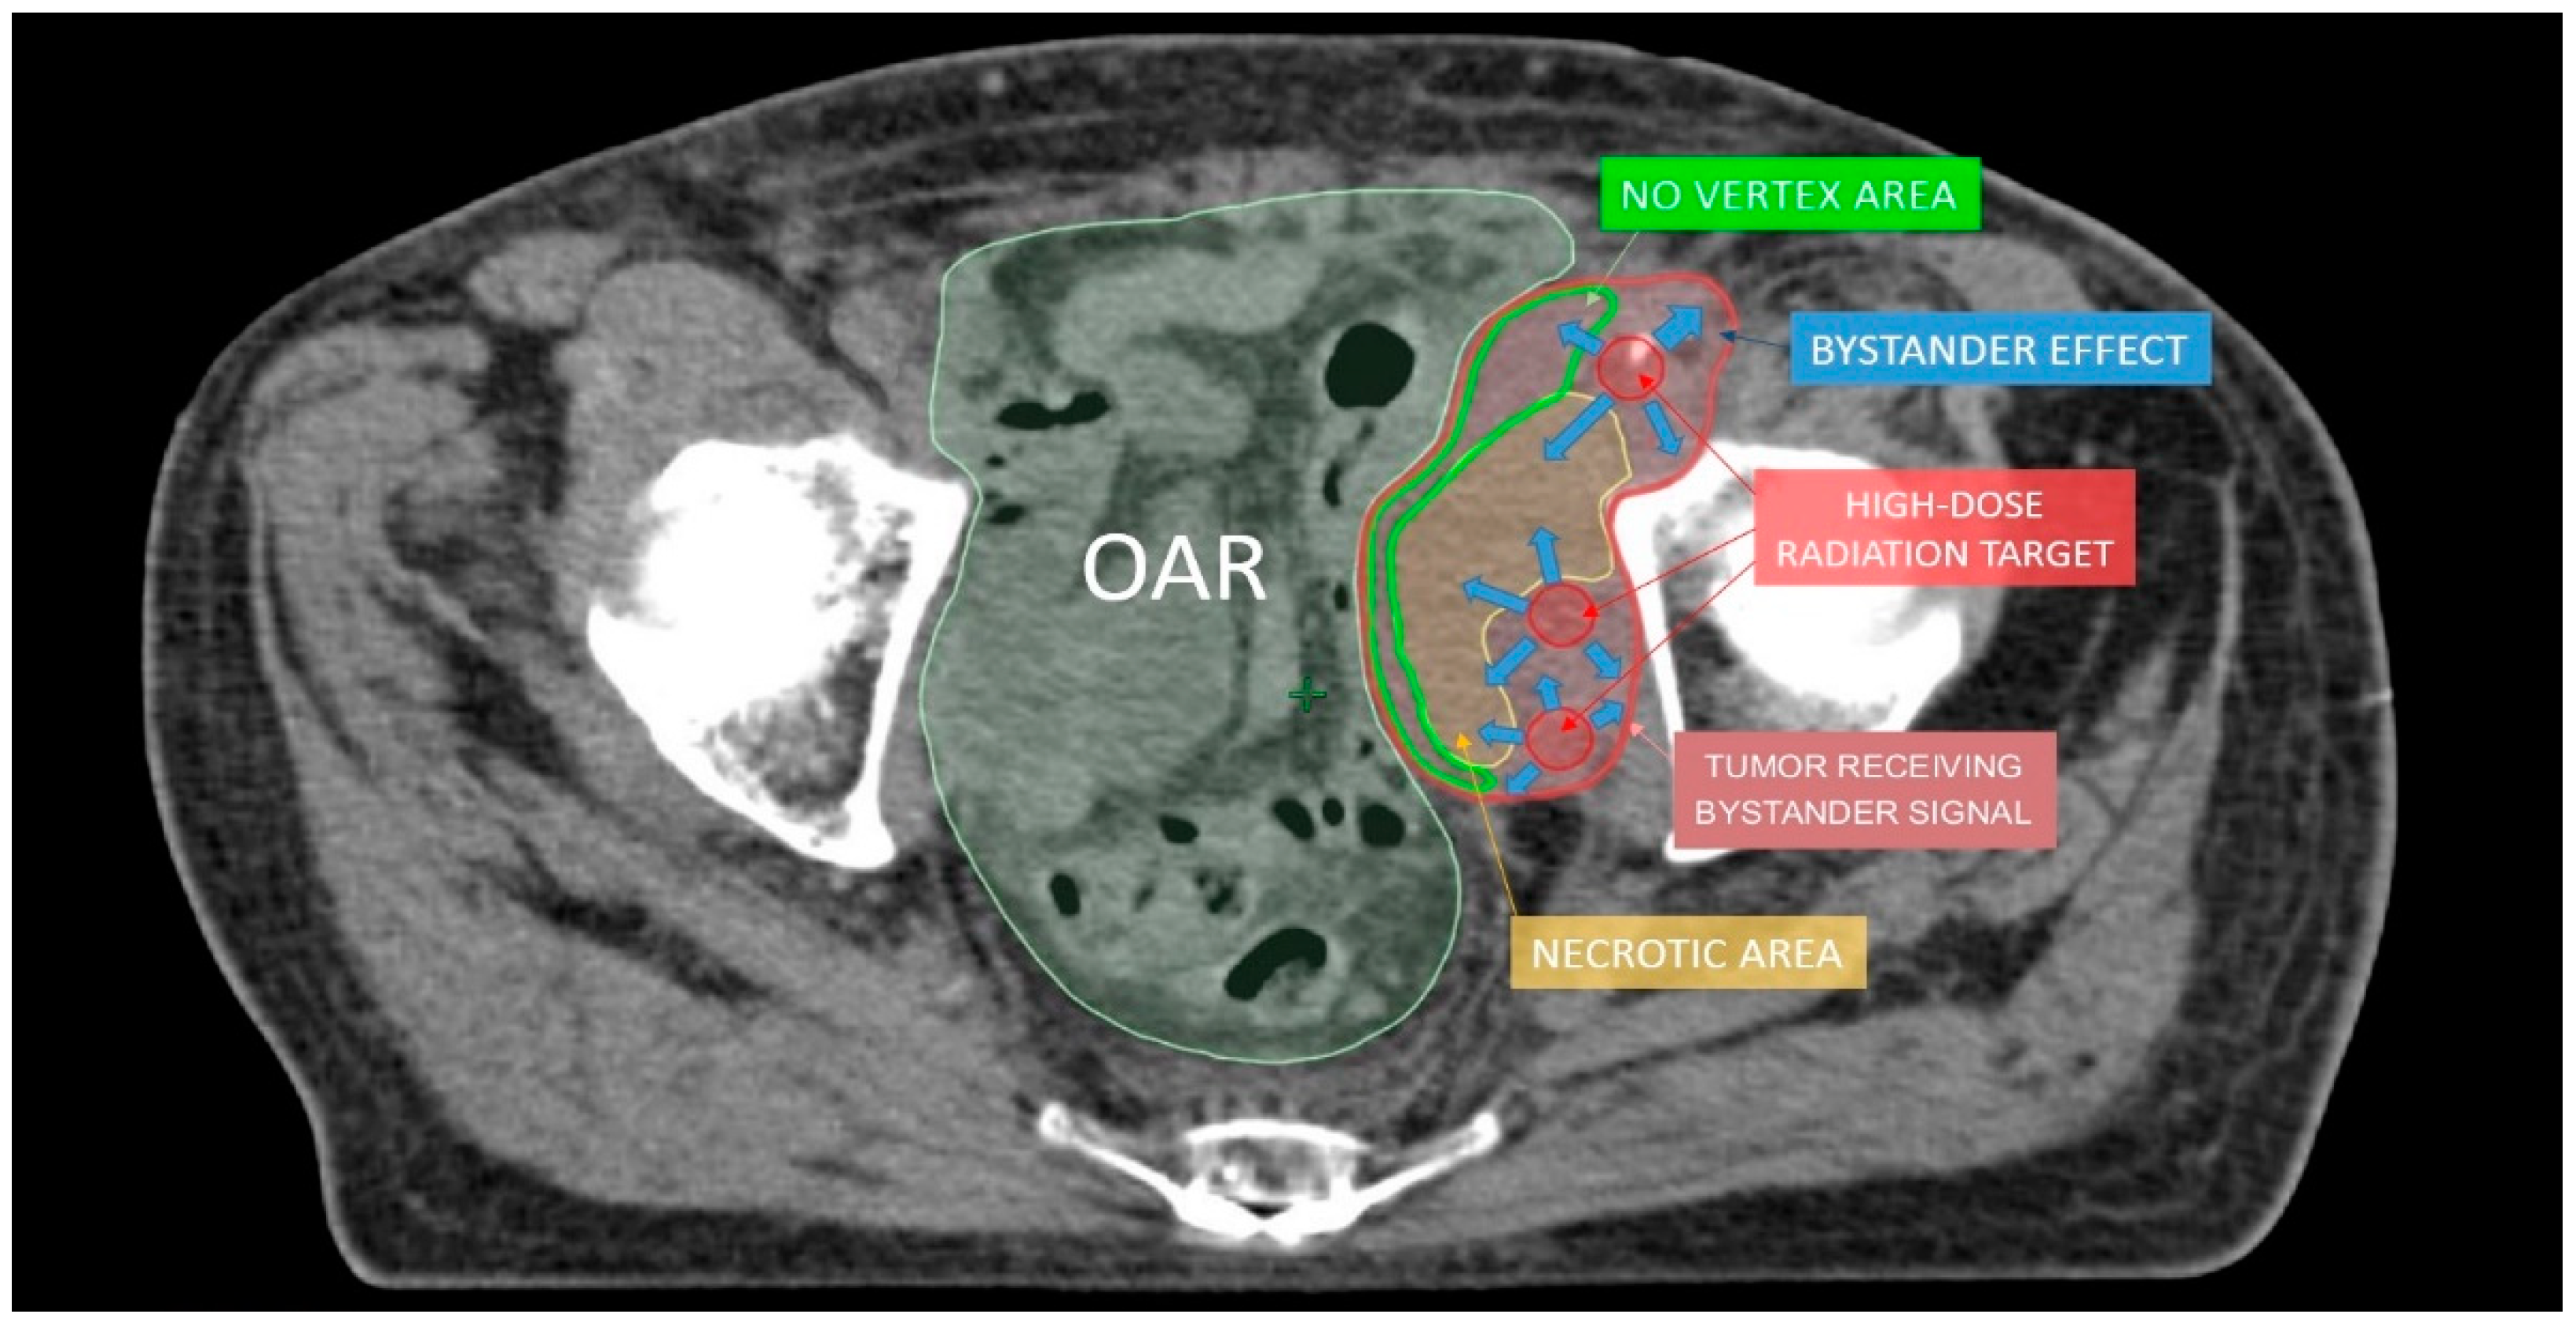

Figure 4.

The hypothesis to explain lattice radiotherapy mechanism: pink line delineates global tumor volume, the yellow line shows the necrotic core, and red spheres represent high dose regions and are approximately located at the boundary between the necrotic and normoxic areas (hypoxigenated interface) to radially elicit the bystander effect (blue arrows), accurately avoiding high dose delivery in the green strip due to the hazardous closeness of bowel (Organ At Risk: OAR).